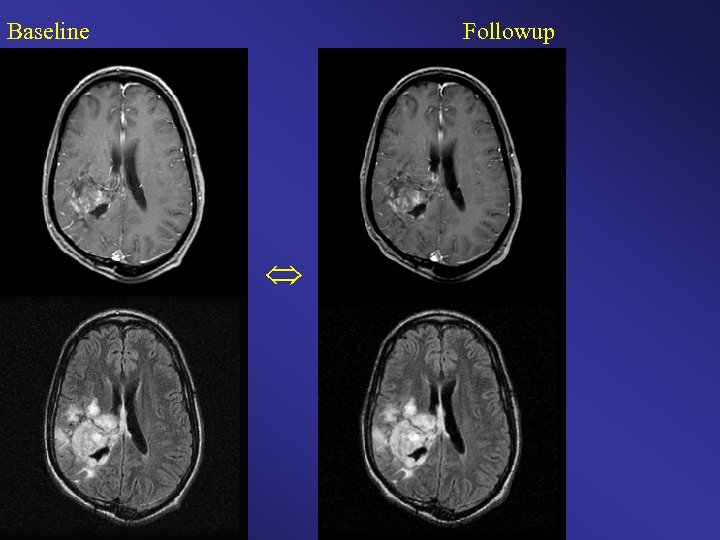

Baseline Followup

Baseline Followup Color Change Map Original Clinical Interpretation: Stable / Time to Progression Diagnosis = 3. 25 months